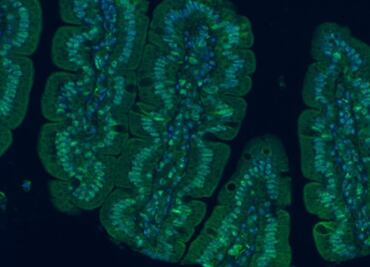

El proyecto MyNewGut muestra la influencia de la microbiota intestinal en el balance energético que regula el peso corporal y en la función cerebral

La microbiota ejerce importantes funciones relacionadas en el cuidado de la salud